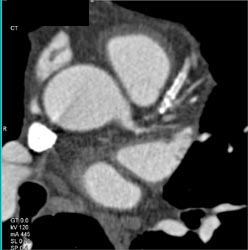

Small Circumflex Artery